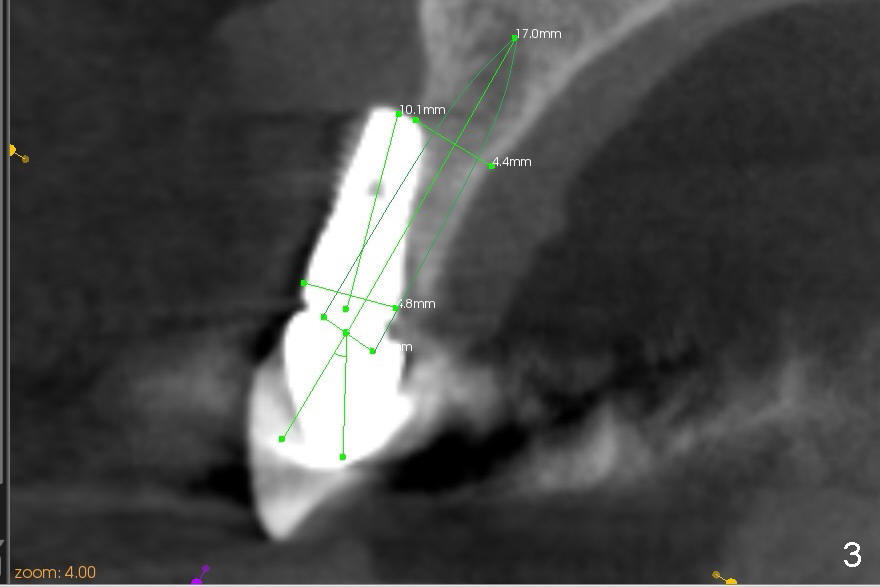

CBCT studies reveal that the implant perforates the buccal plate at the site of #7 and that there is still enough bone to support 3.0x17 mm one piece implant (Fig.2,3).  There is limited bone apical to the tooth #6.  The implant should be at least 17 mm for bone level and 14 mm for tissue level (Fig.4) or preferably 20 mm with sinus lift (Fig.5).  The diameter will be 4.5 mm (Fig.6) or 5 mm (Fig.4.5).